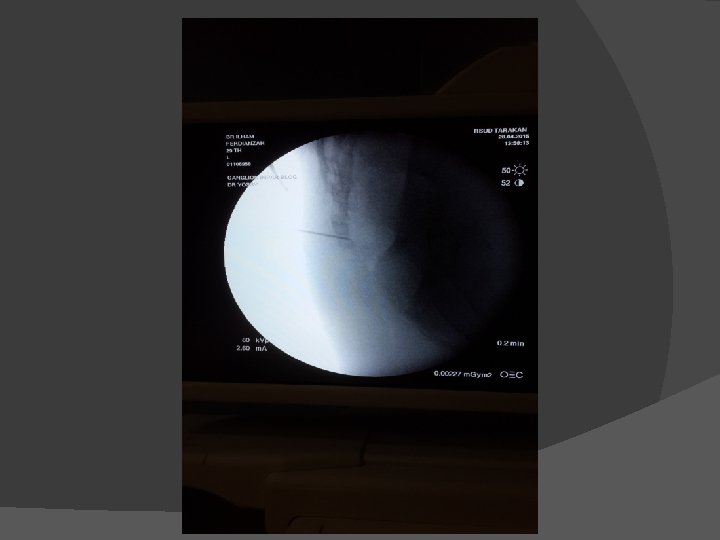

� Kasus 4 laki-laki, 27 tahun didiagnosis dengan adeno ca recti. Mengeluh nyeri disekitar anal selama 6 bulan. Sudah menjalani operasi dan kemoterapi. Selama ini mendapat terapi morfin oral namun masih mengalami nyeri dan mual muntah. Ganglion Impar neurolisis